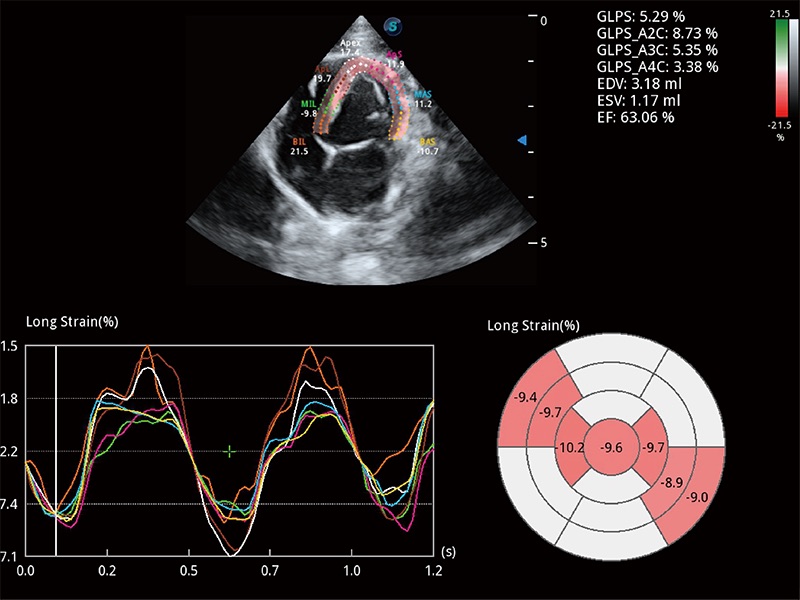

• MQA 心肌定量分析

通过心肌识别技术与二维斑点追踪技术相结合,对心脏的超声图像进行量化分析。计算心肌17个节段的应变、应变率、速度、位移等,并通过牛眼图的形式进行呈现。

(犬)四腔心MQA